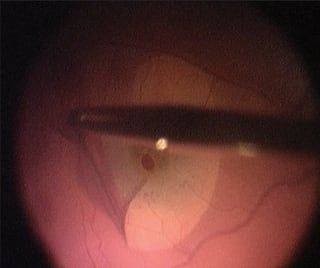

Finally, Membrane Blue is helpful during vitrectomy for floaters or vitreomacular traction, by staining the vitreous and allowing clear visualization of the posterior hyaloid (Figure 4). In patients with floaters, leaving even a moderate amount of vitreous behind may leave the patient dissatisfied with their residual floaters. Using Membrane Blue staining of the vitreous confirms that a vitreous detachment is present and that only the far peripheral vitreous is left in place. In cases of vitreomacular traction, there can be schisis cavities in the vitreous cavity. It may be easy for the surgeon to feel that the vitrectomy is complete, while only removing a portion of the vitreous schisis cavity. Membrane Blue staining reveals the remaining vitreous. In diabetic vitrectomy, it is of utmost importance to remove the posterior hyaloid. Again, staining and identification of residual hyaloid with removal will provide better long-term outcomes in diabetic vitrectomy.

Figure 4. Membrane Blue stained posterior hyaloid grasped and elevated with the vitrectomy cutter.